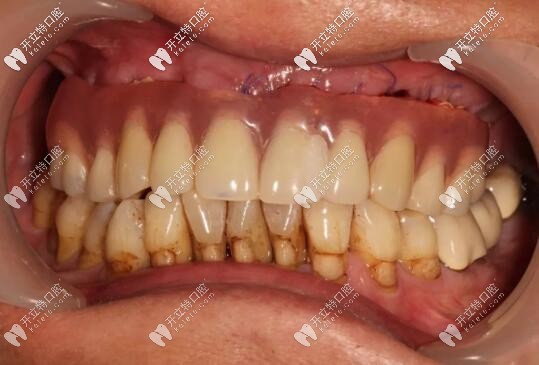

目前已完成ALL-ON-4即刻負(fù)重,通過手術(shù)情況來看,效果確實比較好,作為一位地道老陜?nèi)耍菹壬母屑ぶ橐缬谘员怼?/p>

修復(fù)后